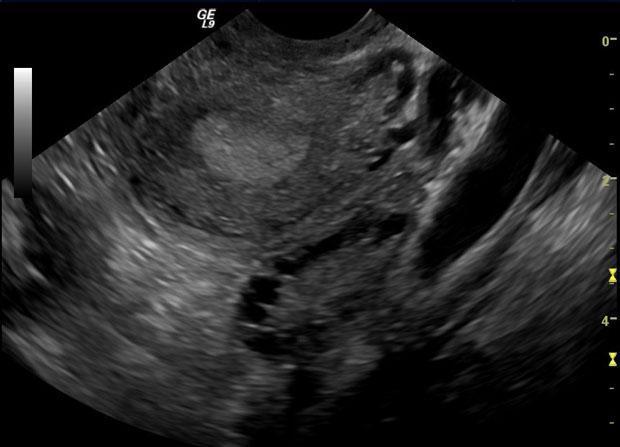

Bu hormonal dengesizlik polikistik over sendromuna pco yumurtalıklarda birçok küçük iyi huylu kist oluşmasına neden olur. Polikistik over sendromlu hastaların kanında normalden fazla insülin bulunuyor ancak vücut hücreleri insüline yeterli yanıt vermiyor. Kadın hastalığıdır ve bu durumda kadınlar normalden daha fazla erkek hormonu üretir. Ayrıca çoğu zaman yaşam kalitenizi etkileyen diğer semptomlara yol açar.

Yumurtlama bozukluğu oluşumuna neden olarak kısırlığa zemin hazırlar. Hormonal bozuklukların yol açtığı p olikistik over sendromu yumurtalıkların androjenleri fazla salgılamasıyla ortaya çıkar. İyi huylu olmalarına rağmen bu kistler dokularda iltihaplanmalara neden olur. üreme çağındaki kadınlarda sık görülür adet düzensizliğine neden olur hamilelik şansını azaltır.

Bunun dışında hipotiroidi akromegali prolaktin hormonunun fazla olması bazı ilaçlar yumurtalık ve adrenal bezdeki bir tümör polikistik over sendromu hirsutizme neden olabilmektedir. Bu durum yumurtalıklarda sağlıklı yumurta gelişimini ve yumurtlamayı bozmaktadır. Polikistik over sendromunun bilinen nedenlerine bakılacak olursa.